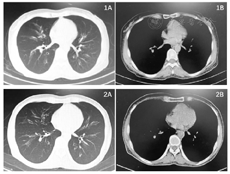

CTPA 2022年3月11日:双肺下叶部分分支动脉管腔内见充盈缺损影;双肺支气管管壁增厚,考虑支气管炎,支气管轻度扩张;双肺上叶数个磨玻璃结节灶;永存左上腔静脉。

CT 2022年3月24日:右侧永存上腔静脉。双肺支气管扩张,右肺下叶后段部分支气管内黏液栓形成可能性大,右肺上叶及左肺多发微结节,考虑增殖灶。

CTPA 2022年4月17日:肺动脉显影不佳,主干、左右肺动脉及其主要分支管腔无明显充盈缺损征象,双肺支气管扩张,左肺上叶尖后段少许炎症(图2)。

对患者近半年诊疗过程中主要检查结果进行总结及分析,患者核心症状为持续呼吸困难,胸部影像学检查提示发病早期的确存在少许肺栓塞征象,初期考虑肺栓塞为呼吸困难的主要病因,但经过治疗后,在肺栓塞征象已消失且D二聚体结果基本正常情况下,呼吸困难并未相应缓解,仍然存在明显气促和呼吸衰竭,且血气分析从早期的Ⅰ型呼吸衰竭逐步变为Ⅱ型呼吸衰竭,不排除呼吸肌的逐步疲劳可能,进一步证明主要病因并非肺栓塞。常见的呼吸困难症状通常为肺部疾病(气道、肺实质、血管、胸膜等)、心功能不全、贫血、神经肌肉病变等疾病首发表现,病因复杂,临床鉴别为难点。该患者有4~8周以上的慢性呼吸困难、呈持续性,程度重,上述全面的检查证据并不支持包括肺部感染、肺血管疾病、慢性气道疾病如COPD或哮喘,胸膜疾病、间质性肺疾病,心衰、或神经肌肉如膈肌功能障碍所导致的呼吸困难。众多检查结果中,少数阳性结果包括胸部CT提示持续存在的支气管扩张,但支气管扩张程度、伴发的感染及痰潴留征象并不重,同临床所见的相似程度的支气管扩张患者存在的呼吸困难程度极为不匹配,因此考虑支气管扩张所导致的肺功能损害或许参与患者呼吸困难,但绝不是主要病因。支气管镜及灌洗病原学同样不支持感染(包括真菌)为其病因。因此,对常见呼吸困难病因进行排除后,结合患者既有天疱疮的诊断,需警惕此病例症状是否与天疱疮有关,即需证明是否为以天疱疮的一类少见亚型闭塞性细支气管炎(bronchiolitis obliterans,BO)特征的肺部受累为特征的PNP所致难以解释的呼吸困难。闭塞性细支气管炎由多种病因所致,其HRCT的典型表现可有肺密度下降的斑片影,伴随着血管口径的减少,即马赛克式灌注或马赛克式减低。且在疾病进展的患者,常会有支气管扩张的征象,CT表现为气道壁的增厚和口径的扩张。因此,考虑这位患者CT的双肺支气管扩张为BO所致可能性大。